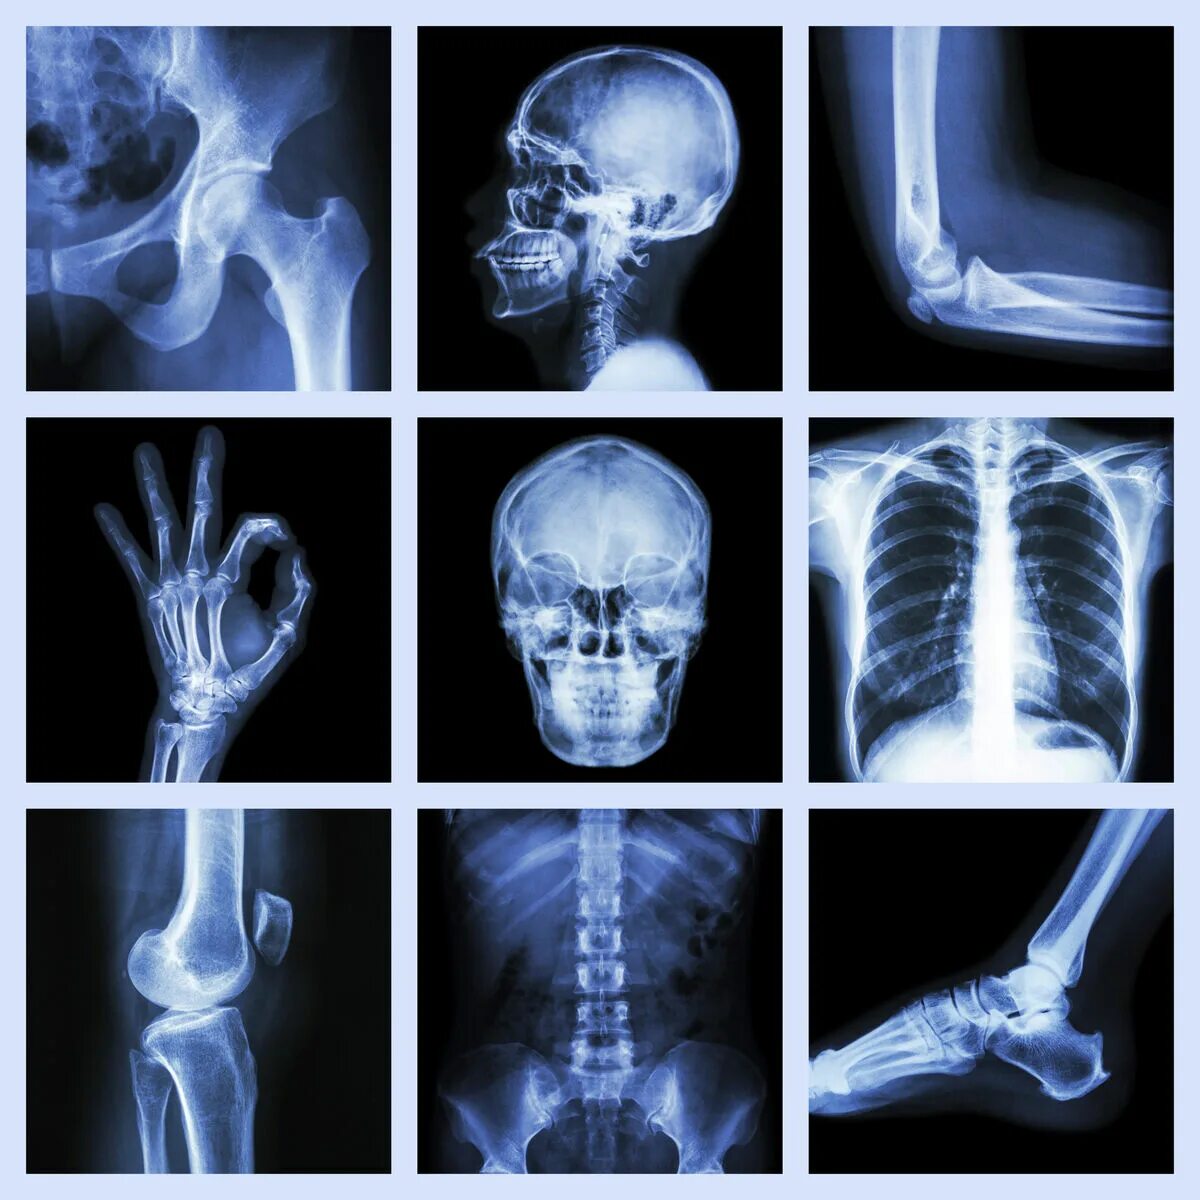

Рентген делают в одежде или нет